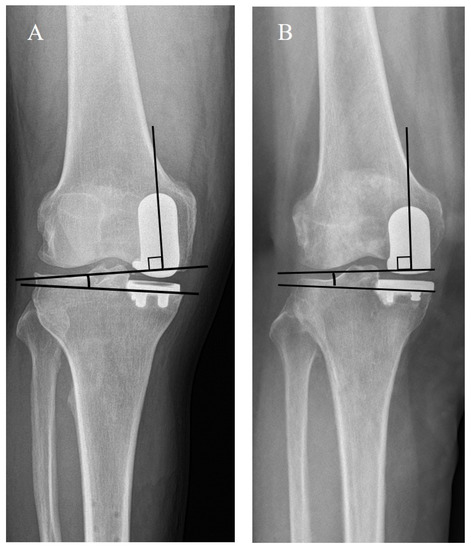

| Coronal femoral component angle (α) (°) | 2.4 ± 4.9 | −1.1 ± 3.2 | <0.001 |

| Coronal FT component congruence angle (°) | 3.4 ± 4.5 | 1.9 ± 2.6 | 0.028 |